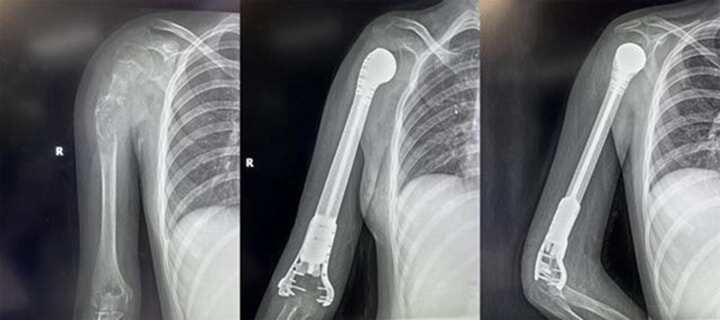

13歲少女患骨肉瘤面臨截肢,3D打印肱骨假體治療成功保肢

2022419日,西安市紅會(huì)醫(yī)院骨病腫瘤科為一名13歲小患者成功實(shí)施了肱骨惡性腫瘤切除3D打印假體重建術(shù)。